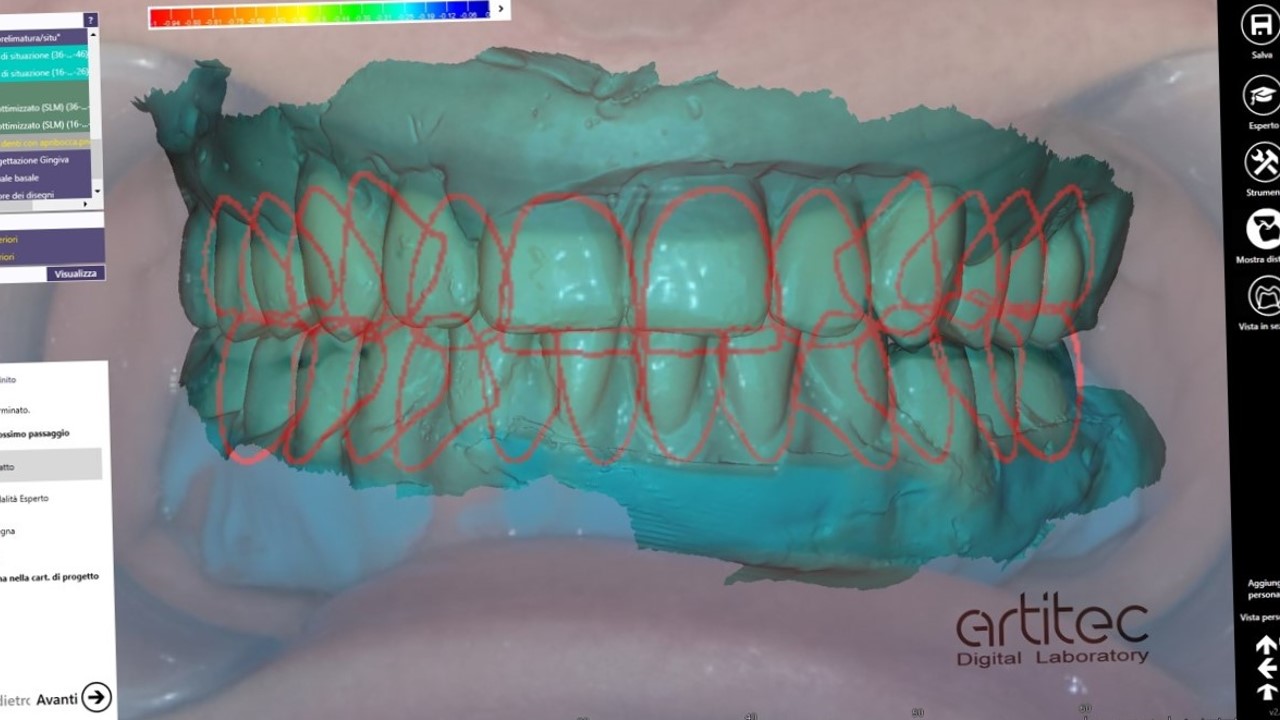

foto 14 outline per definire volumi protesici

foto 15 progetto protesico ultimato

La fase protesica inizia con la ribasatura delle protesi provvisorie per rilevare la corretta anatomia della cresta. Quindi si procede a scansionare con scansione intraorale le impronte ottenute fuori dal cavo orale, poi le protesi provvisorie ribasate ricollocate nel cavo orale e la loro occlusione. Infine, si scansionano le creste edentule dopo aver posizionato gli scan body per tecnica digitale per rilevare la posizione degli impianti. Per la pianificazione sono scattate delle fotografie intraorali ed extraorali per la definizione dei limiti perimetrali del volto al fine di poter eseguire la programmazione del caso tramite il software di previsualizzazione. Le scansioni così ottenute sono poi inviate al laboratorio per la realizzazione di un prototipo delle protesi in prova.